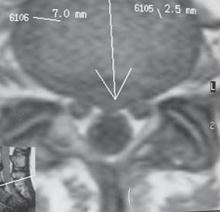

На МРТ № 18 наблюдаются грыжи межпозвонковых дисков в сегментах: — LIV-LV вентральной локализации с образованием каудального секвестра; при расположении межпозвонковой грыжи на один сегмент выше, «конфликт» с брюшной аортой был бы неизбежен; — LV-SI — дорсальная грыжа межпозвонкового диска, частично компенсированная спондилёзом МРТ № 19 ![]() МРТ № 20 ![]() На МРТ № 19 наблюдается дорсальная грыжа межпозвонкового диска шейного отдела позвоночника в сегменте СV-СVI с компрессией спинного мозга На МРТ № 20 наблюдается грыжа межпозвонкового диска шейного отдела позвоночника в сегменте CV—CVI и протрузия в сегменте CVI-CVII Замечу, что если грыжа межпозвонкового диска имеет достаточно большой размер и локализована в шейном отделе, то она способна вызвать не только соматические нарушения, но и даже психические расстройства. Причина кроется в сдавлении дурального мешка грыжей межпозвонкового диска (дуральный мешок — это герметичный соединительнотканный мешок, формируемый твёрдой мозговой оболочкой, в котором расположен спинной мозг). Как известно, спинной мозг не имеет болевых рецепторов. Однако вышеуказанная патология приводит к локальному устойчивому возбуждению определённых зон коры головного мозга. На субъективном уровне это может проявляться как постоянное чувство тревоги (так называемый «синдром ожидания»). Грыжи межпозвонковых дисков в грудном отделе позвоночника явление довольно редкое, но всё же наиболее опасное. Опасное потому, что эпидуральное пространство в грудном отделе позвоночника узкое по сравнению с другими отделами, в пределах всего 0,2–0,4 см по всей окружности дурального мешка (твёрдой оболочки спинного мозга). Поэтому даже небольшое грыжевое выпячивание может сдавить спинной мозг и вызвать тяжелейшие осложнения. Но, как уже говорилось, это явление в грудном отделе позвоночника редкое, поскольку высота межпозвонковых дисков довольно мала, всего около 3–5 мм, да и грудной отдел позвоночника менее подвижен по сравнению с другими отделами за счёт жёсткого рёберного каркаса, а значит, менее подвержен травматизации. МРТ № 21